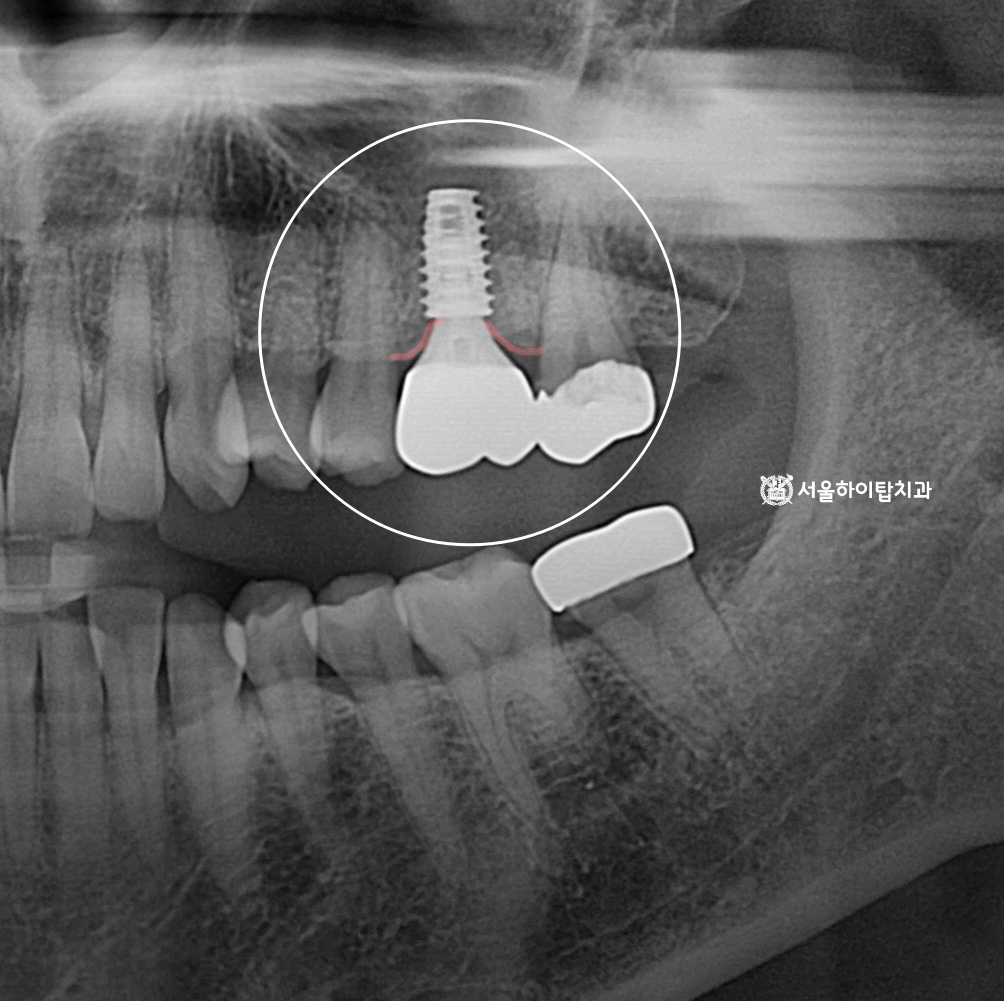

임플란트 식립 완료

만수동 치과 에서는 상기 시뮬레이션을 통해 계획된 위치에

임플란트가 안전하게 식립된 모습을 확인할 수 있습니다.

이후 약 3~4개월간 ‘골유착'(Osseointegration) 과정이 이루어지며,

이 기간 동안 임플란트 픽스처가 주변 치조골과

점차 단단하게 결합하게 됩니다.

특히 식립 4주 전후에는 엑스레이를 통해

픽스처가 위치 변화 없이 안정적으로 유지되고 있는지,

염증 소견은 없는지 등을 다시 한 번 확인하여

예후를 평가하게 됩니다.